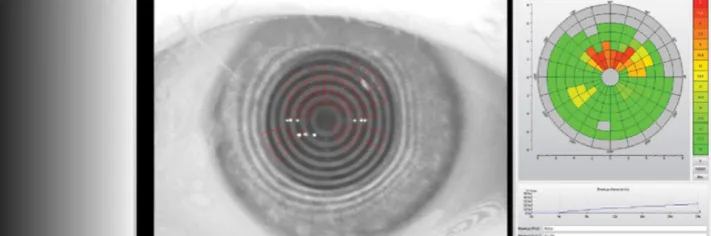

Konieczność oceny efektu refrakcyjnego przed doborem drugiej soczewki

W niektórych przypadkach, zwłaszcza gdy pacjent ma bardzo wysokie oczekiwania co do widzenia bez okularów po operacji (np. planuje soczewki toryczne lub wieloogniskowe), konieczne jest dokładne ocenienie ostatecznego wyniku refrakcyjnego (wady wzroku) po pierwszej operacji. Stabilizacja widzenia i pomiary refrakcyjne pierwszego oka pozwalają na optymalne dobranie soczewki do drugiego oka, co może wymagać dłuższego odstępu (np. 6-8 tygodni). Dzięki temu możemy dążyć do jak najlepszego wyniku i zminimalizować resztkową wadę wzroku.